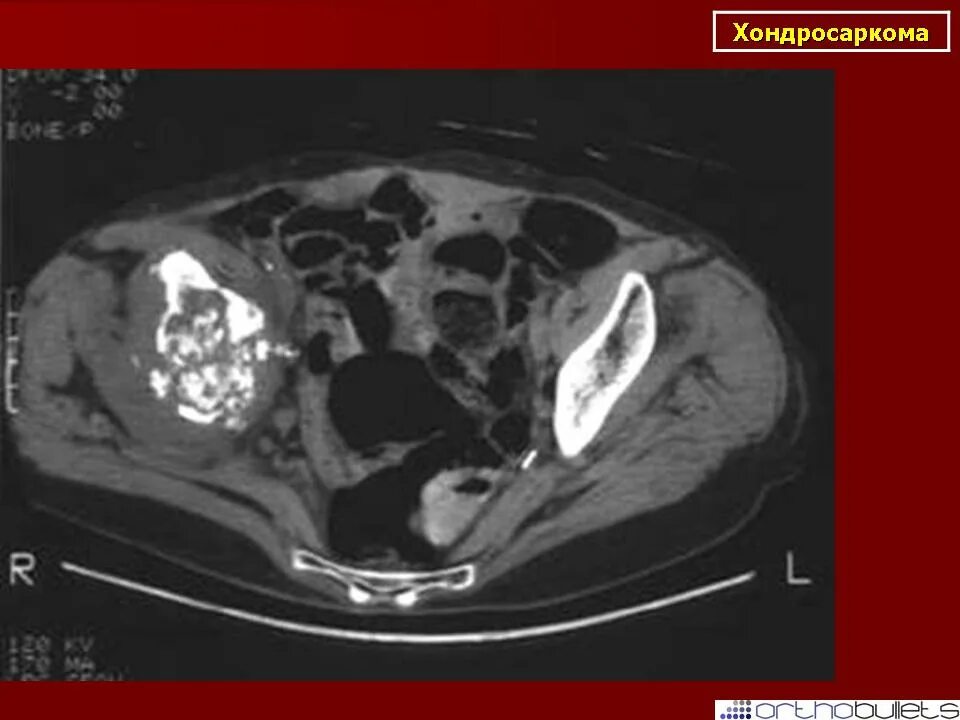

Саркома мрт